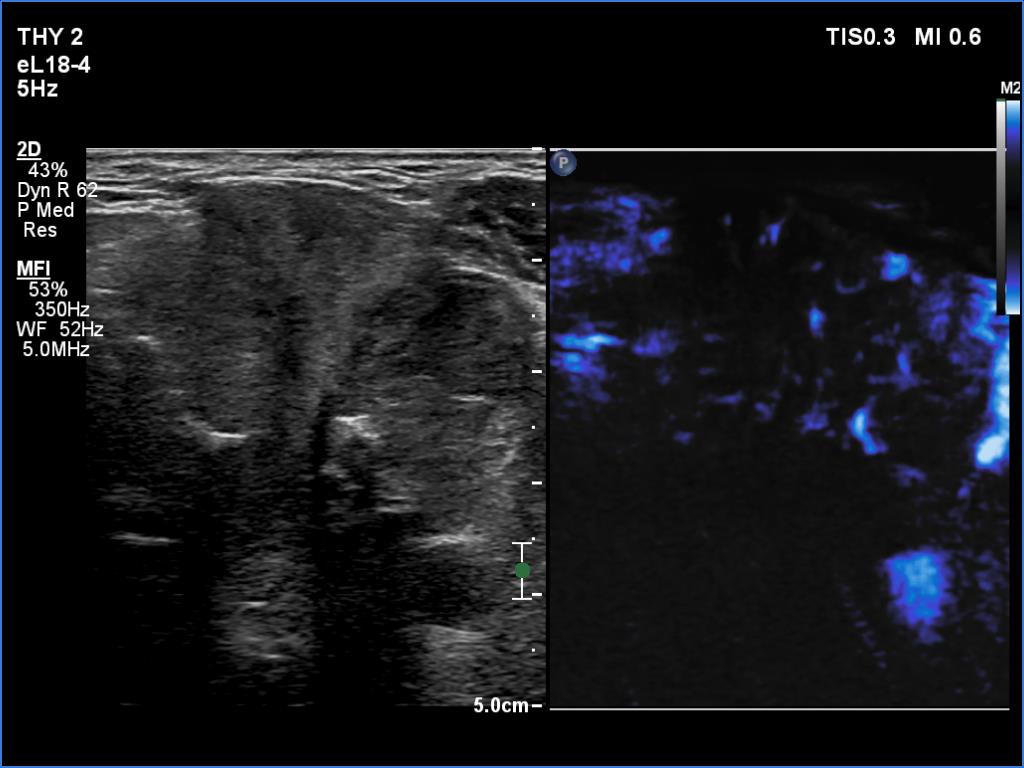

Ultrasonography. The right lobe was echonormal and intact. A large mass occupied almost the entire left lobe. On this side, normal thyroid tissue could only be identified in the dorsal part. The mass was composed of echonormal and hypoechoic areas, had macrocalcifications, irregular intranodular vascularity and proved to be very hard on elastography. There were multiple lymph nodes in III, IV and V left neck compartments. One of the nodes was in close proximity to the jugular vein and was suspicious of having broken into the vessel. The trachea was significantly narrowed at the lower level of the thyroid.

2. There are several remarkable findings in this case, e.g., the destruction of the left lobe by the tumor, the elastography pattern, the relation of the largest metastatic lymph node and the jugular vein, the ultrasound demonstration of the trachea' stricture.